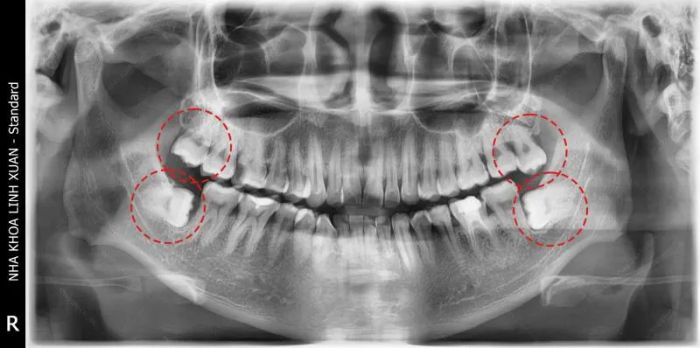

Wisdom teeth, also known as third molars, are complex due to their deep roots and multiple ligaments. If your wisdom tooth is impacted, you need to visit a dentist for prompt treatment. At Linh Xuân Dental, patients receive thorough exams and X-rays. If the tooth is abnormal, extraction will be recommended. If the tooth is newly erupted and not affecting health, you'll receive guidance on managing pain during the eruption.

With the focus on patient health, Linh Xuân Dental is trusted by the residents of Thu Duc City for oral care. The clinic’s team, with over 15 years of experience, has successfully performed wisdom tooth extractions for thousands of patients. Before the extraction, patients’ medical history will be carefully reviewed, especially for those with heart conditions, blood disorders, or anesthesia allergies. In such cases, blood tests and drug allergy tests will be conducted to ensure safe procedures.

At Linh Xuân Dental, wisdom tooth extractions are carried out in a sterile minor surgery room equipped with modern technology, such as Piezotome bone surgery equipment, PRF, and ConeBeam CT 3D imaging, ensuring a safe and precise extraction process.